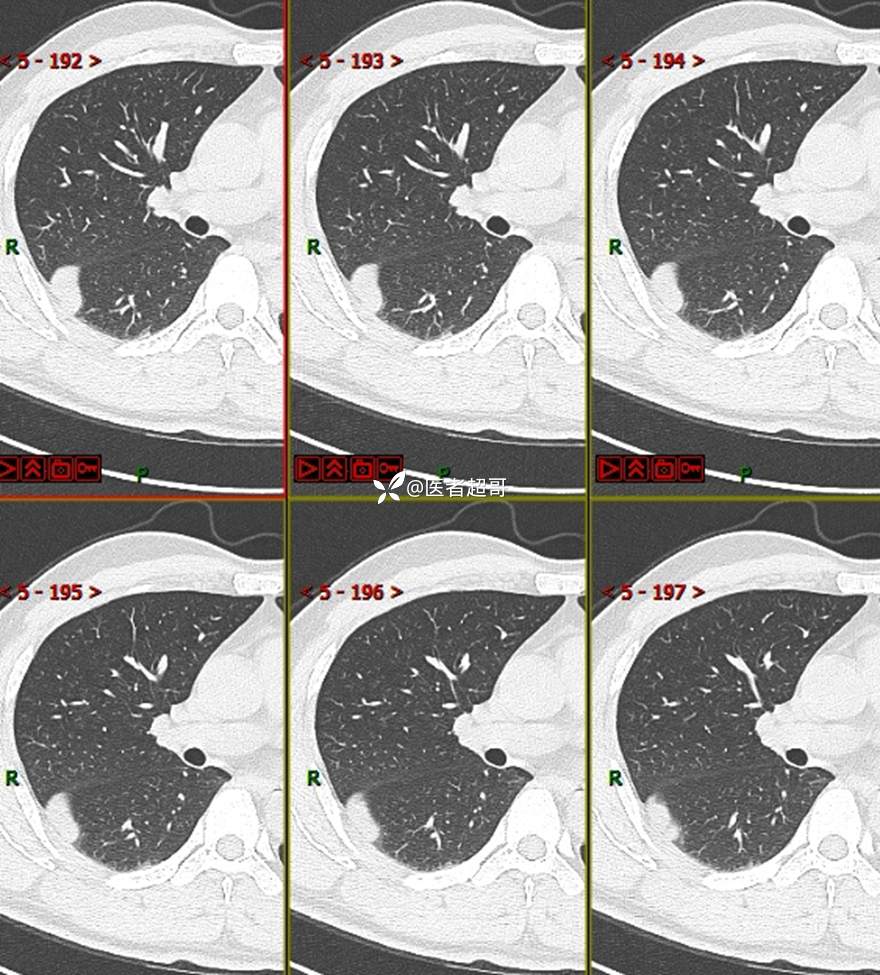

现病史:患者1年余前于体健中心行胸部X片发现右上肺叶密度增高影,无明显咳嗽,咳痰,无痰中带血及咯血,无胸痛及胸闷、气短,无发热、盗汗及全身乏力。无头痛、头晕,无腹痛、腹胀及恶心、呕吐,无声音嘶哑及呛咳,未行特殊治疗。后患者定期复查胸部CT,未见明显变化。2023-2-6患者于我院复查胸部CT:右肺上叶、下叶交接处胸膜下见实性结节影,最大截面约2.6cm×1.4cm,较前增大,建议行手术治疗。今为求进一步诊治,遂来我院就诊,门诊以“肺肿物”收入我院,患者自发病以来,神志清,精神可,饮食可,睡眠良好,大小便正常,近期体重未见明显增减。